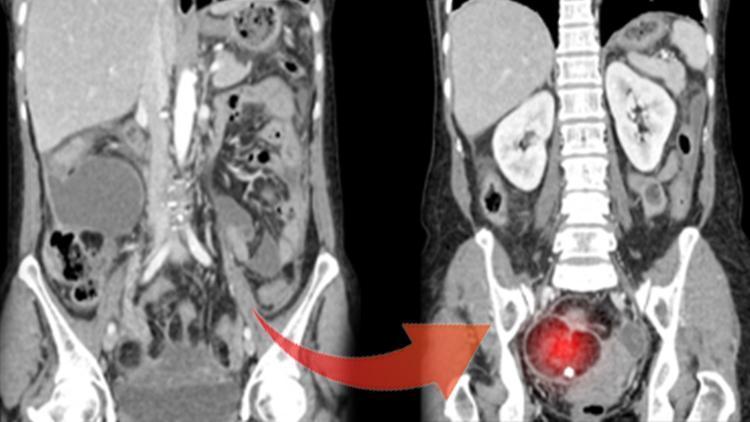

Şekil 1-Dermoid kistli yumurtalık Şekil 2-Normal yumurtalık